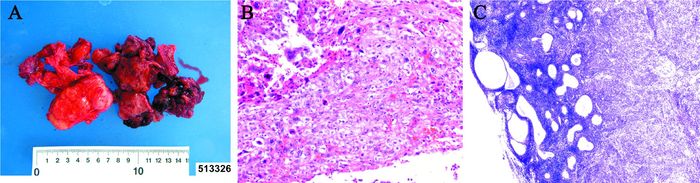

临床诊断:盆腔肿物(不排除恶性)。入院后完善检查,确认患者无手术禁忌证后,于2014年12月29日在全身麻醉下行剖腹探查术。术中见:盆腔积血约100 ml,右侧卵巢肿物形态不规则,大小约5 cm×6 cm×3 cm(图 1A),已破溃,质地糟脆,呈烂肉样侵蚀在部分肠管表面,且与后腹膜粘连。取出游离破碎的卵巢肿物,吸净盆腔内积血,见盆腔粘连,直肠右侧壁、小肠系膜有类似病灶。子宫萎缩,钝性分离直肠右侧壁与右卵巢及肿物粘连处,左侧附件及右侧输卵管未见明显异常。钝性剥除直肠右侧壁病灶,将游离破碎的卵巢肿物和直肠右侧壁病灶一并送检快速病理。术中冰冻检查结果为:(右侧卵巢、直肠右侧壁)癌,分化差(图 1BC)。术中诊断:右侧卵巢癌,即行全子宫、双侧附件、大网膜、阑尾切除术,双侧输尿管旁病灶切除术,回盲部病灶切除术,小肠系膜转移灶切除术,盆腔及腹主动脉旁淋巴结清扫术,无肉眼残留病灶。病理检查结果回报:(右卵巢)癌肉瘤,以高级别多形性肉瘤为主、伴有少量低分化癌,右卵管、直肠右侧壁见肿瘤浸润;双侧输尿管旁病灶、右侧回盲部病灶、小肠系膜病灶内见肿瘤浸润;左侧附件未见明显病变,萎缩性子宫内膜,慢性子宫颈炎,慢性阑尾炎,浆膜面见肿瘤浸润,大网膜未见明显病变,右髂内1枚淋巴结见肿瘤转移,左闭孔、右闭孔、左髂内、左髂外、右髂外、左髂总、右髂总、左腹股沟深、右腹股沟深、腹主动脉旁的淋巴结均未见肿瘤转移。临床诊断为卵巢癌ⅢC期。

图 1 一例卵巢癌肉瘤的手术切除标本及病理切片图 A:肉眼观肿瘤组织;B:病理切片(苏木素-伊红染色,×200);C:病理切片(苏木素-伊红染色,×100)